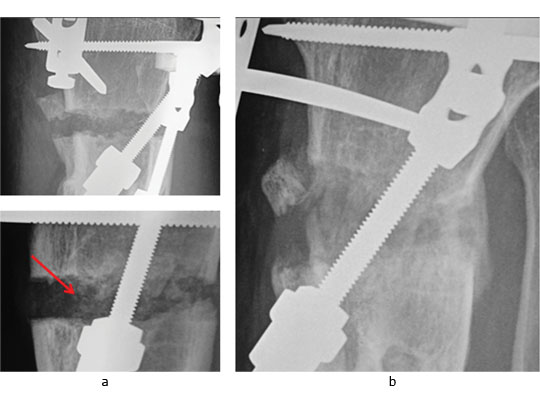

The potential of this approach is seen in the challenging case of a 51-year-old presenting with the combination of established proximal tibial malunion and ACL defi cient instability can be challenging to treat. The patient had a long standing varus malunion and a 3 cm shortening of his tibia presented with pain, instability and deformity. The patient’s medial compartment was bereft of any articular cartilage. We used a modified Taylor Spatial Frame for osteogenesis which we augmented with stem cell therapy. Application of a Taylor Spatial Frame in combination with tibial and fibular osteotomies was followed with distraction osteogenesis at a rate of 1 mm per day, commenced the day after the tibial and fibular corticotomies. We supplemented the standard treatment with stem cell therapy one week following corticotomies. Autologous PBSC were harvested from the patient and injected percutaneously into the corticotomy sites. We were able to demonstrate callus formation two weeks after distraction osteogenesis (one week after injection of PBSC, Fig.4a). Two further weekly injections of PBSC were given during the osteogenesis process and almost complete healing was seen at four months (Fig.4b). Although a similar result could have been easily achieved without the injection of PBSC there is the potential to reduce frame time and morbidity associated with extended frame wear. At final follow-up the patient did not have any equinus deformity of the ankle or a loss of initial knee movement, regaining 50° of knee range of movement following the distraction osteogenesis. A second-stage arthroscopy with subchondral drilling and allograft ACL reconstruction was performed for chondrogenesis and stabilisation of his knee. We did not see any premature closing of the corticotomy with the use of PBSC and we believe that PBSC may have a significant future role in malunion and nonunion surgery.

Fig. 4 Radiographs of a 51-yearold man who presented with left knee pain and instability, showing a) distraction osteogenesis and evidence of callus formation one week after injection of PBSC into corticotomy site (red arrow), and b) signifi cant growth of new bone after four months.